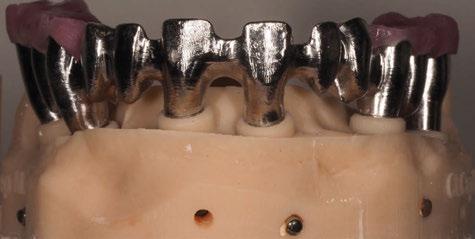

y lo que se pudo preservar del hueso malar. Se añadió una malla sinterizada infraorbitaria para dar volumen a la mejilla y se planificaron dos brazos de conexión que emergieran en las posiciones 24 y 26 de forma subgingival (Figuras 8 y 9). La superficie interna que apoyaba en el hueso era de titanio microrrugoso, y la superficie externa y conectores de titanio pulido y hexágono externo universal (Figuras 10 y 11). La cirugía se hizo bajo anestesia general en infiltración con anestesia local (4% articaína, 1:100.00 epinefrina), levantando el

Figura 10. Visión vestibular de la estructura con conexiones en titanio pulido.

Figura 11. Visión posterior de la estructura con titanio rugoso en contacto con el hueso.